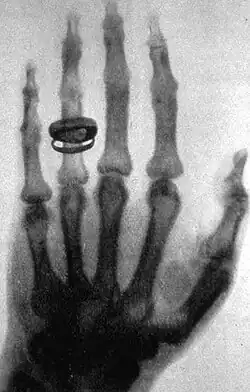

Havendo notando que enquanto segurava os objetos entre o tubo e écran de platinocianeto de bário tinha visto a imagem dos ossos de sua mão, Rontgen decidiu investigar sobre este assunto para isto convenceu D. Bertha, sua esposa, a colocar a mão sobre um filme fotográfico em chassi de papel e ligou o tubo durante 15 minutos. O filme revelado mostrou claramente a imagem dos ossos e uma nova era na ciência estava inaugurada.

Ciente da importância de sua descoberta, que ele chamou de raios X por não saber realmente do que es tratava, sendo X a incógnita da matemática, Prof. Röntgen passou os últimos dias de dezembro a redigir o artigo que submeteu ao Secretário da Sociedade Físico-Médica de Wurzburg, solicitando sua publicação no SITZUNGSBERICHTE da Sociedade, embora não tivesse o trabalho sido apresentado em uma das reuniões da Sociedade. Assim foi feito e no exemplar de dezembro de 1895 daquela revista saiu publicado o "EINE NEURE ART VON STRAHLEN" (sobre uma nova espécie de raios).